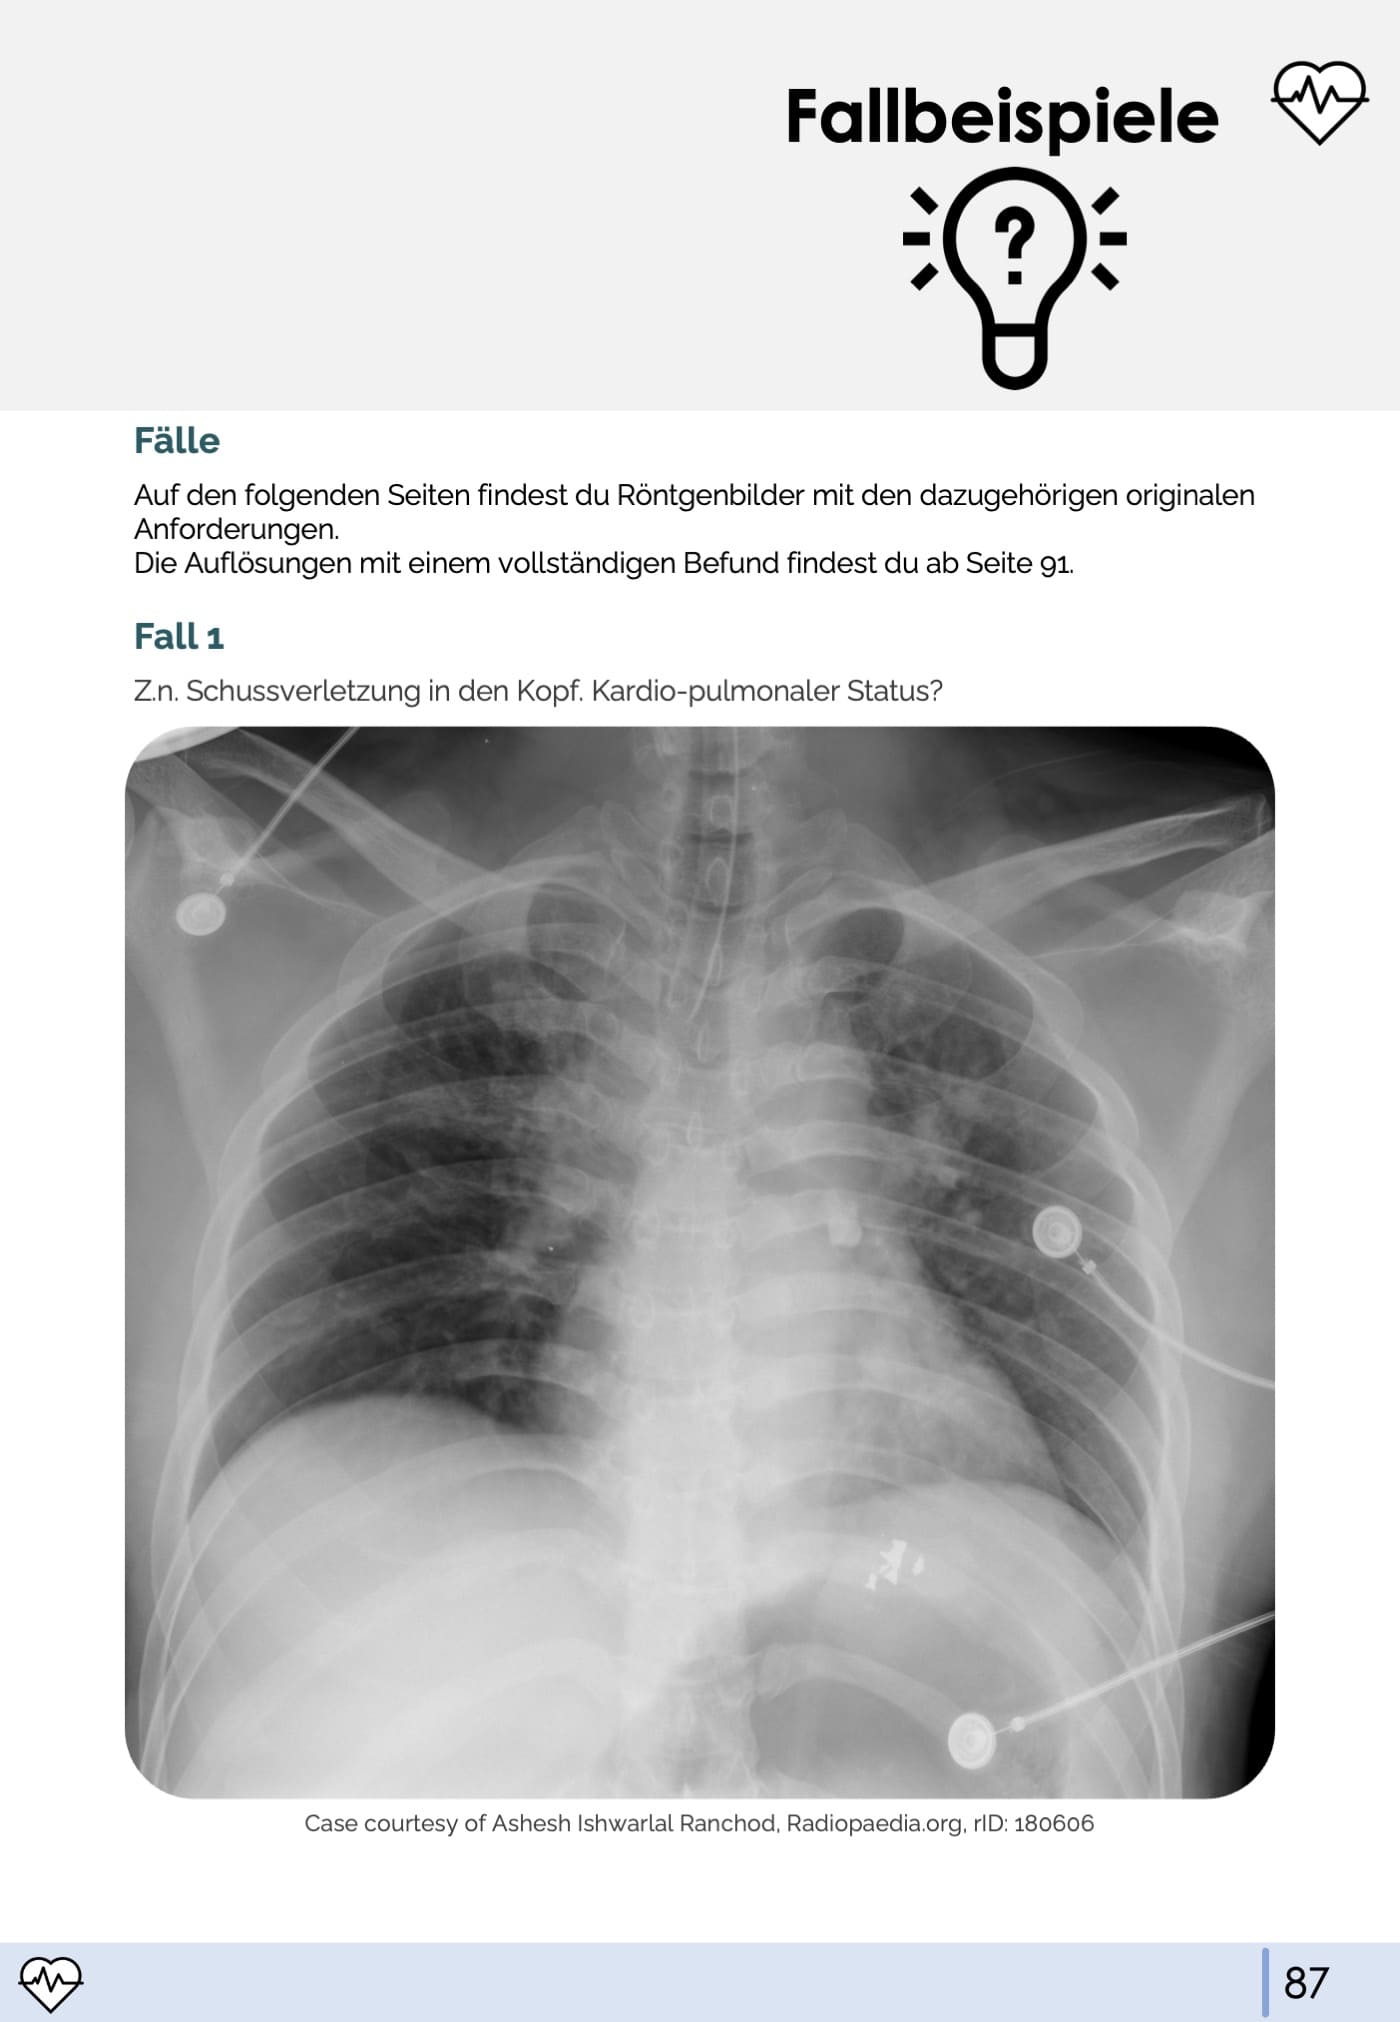

Angefangen bei den absoluten Grundlagen (z.B. Bildentstehung, Normalbefund und Qualitätskriterien) über Befunde, die jeder erkennen sollte (z.B. Pneumonie, Lungenödem/Stauung) bis hin zu Spezialbefunden (z.B. Sarkoidose, Tuberkulose) ist alles dabei. Zum Üben der praktischen Bildinterpretation gibt es auch ein Kapitel mit Fallbeispielen und Originalbefunden.

- 9. Fallbeispiele